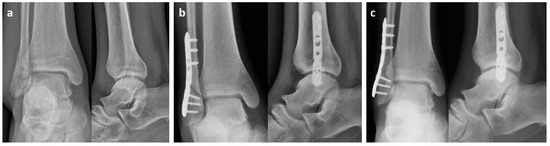

2.1. Surgical Procedure

3. Results